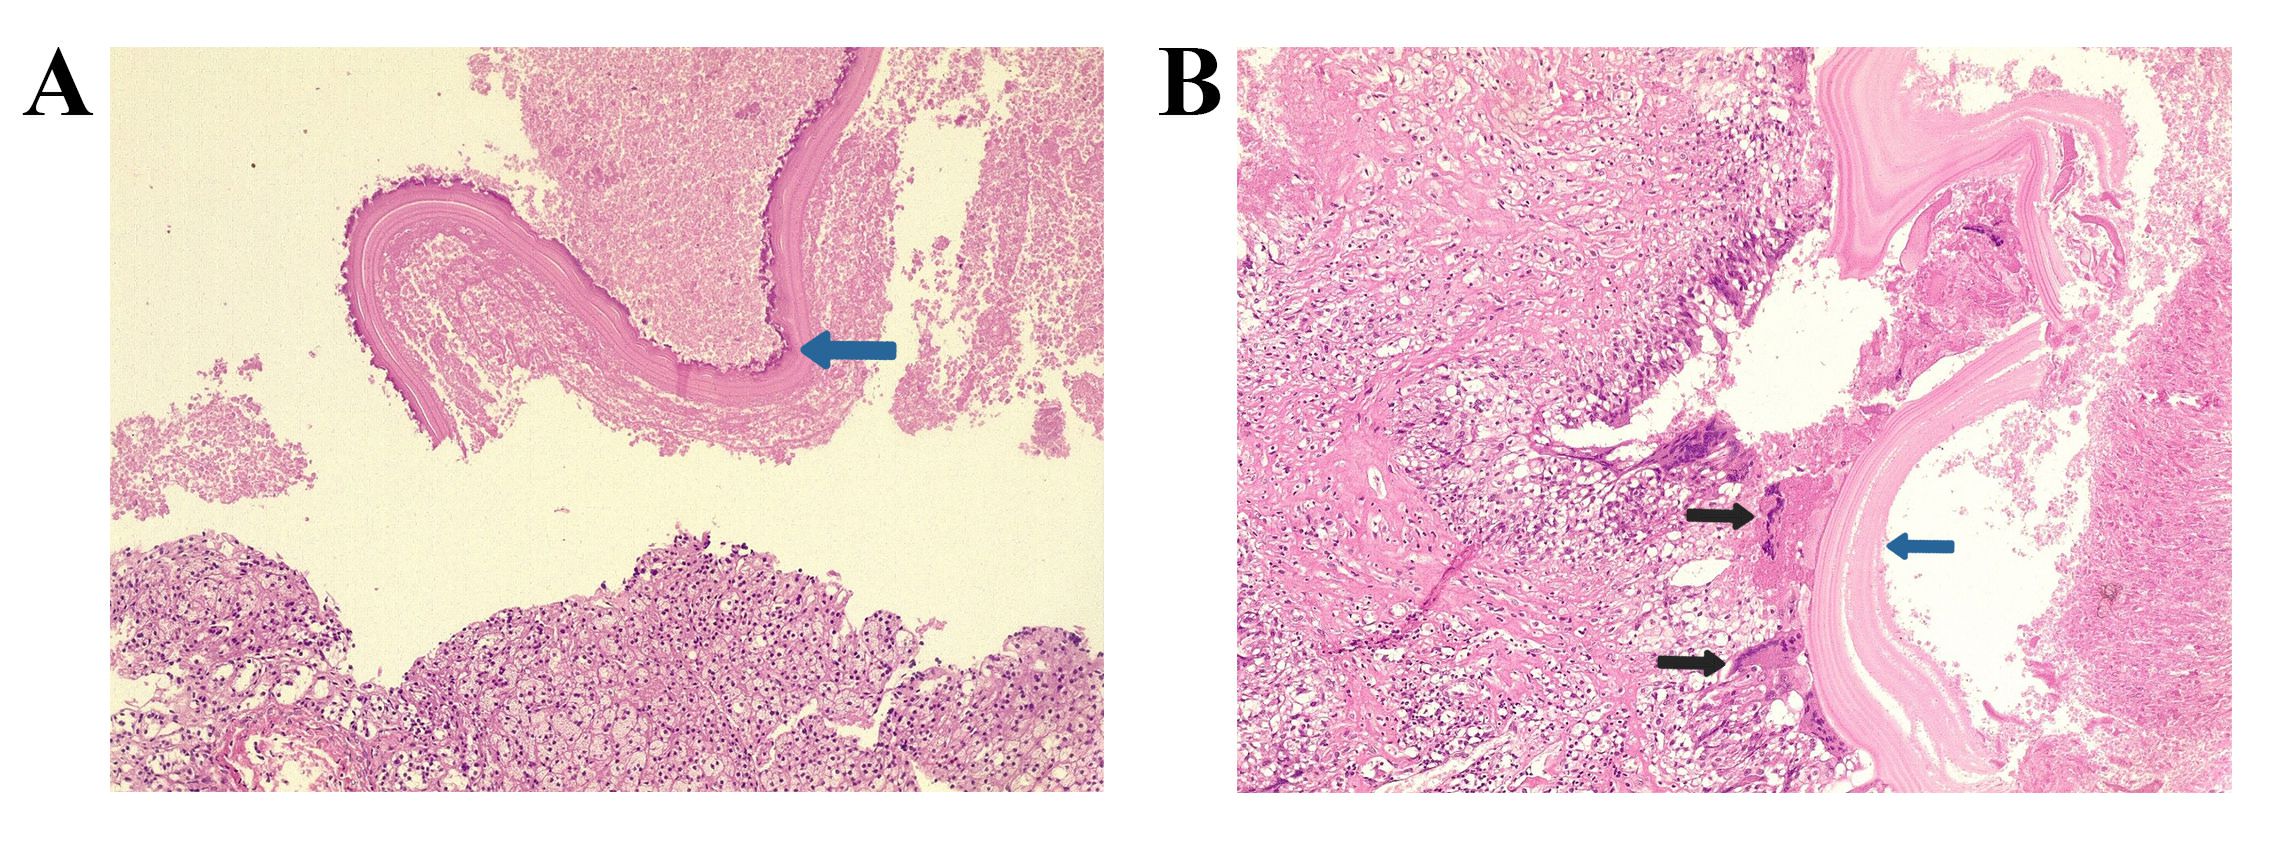

The primary diagnostic tool for thyroid nodules is FNA, which often leads to the misclassification of HTT as PTC or medullary thyroid carcinoma [9]. Ito et al. suggested that this diagnostic confusion arises from shared cytological features, including intranuclear cytoplasmic inclusions and nuclear grooves, which represent hallmark characteristics of PTC [4]. The cytological appearance of HTT on liquid-based preparations reveals cohesive aggregates or syncytial fragments of tumor cells surrounding hyaline material. Although tumor cells in HTT show enlarged nuclei with hyperchromasia and occasional intranuclear pseudo-inclusions similar to papillary carcinoma, HTT cells typically display dispersed fine chromatin rather than the pale and clear chromatin pattern observed in PTC [9].

Additionally, HTT cells demonstrate less frequent nuclear membrane irregularity and exhibit a more stratified trabecular arrangement compared to papillary carcinoma. These subtle distinctions prove crucial for accurate cytological interpretation, though they remain challenging to discern consistently in clinical practice [9]. Dell’Aquila et al. reported that up to 75% of HTTs are classified within Bethesda categories IV to VI [12]. Among the cases included, two were diagnosed as Bethesda category IV, while three were classified as category V, emphasizing their frequent misinterpretation by cytopathologists. Equivocal cytomorphologic diagnoses, such as atypia of undetermined significance or follicular lesion of undetermined significance, require repeat FNA, as the malignancy risk for nodules in these categories ranges from 1% to 15% [8].

On gross examination, HTT typically presents as a solid, well-circumscribed mass, or less commonly, as an encapsulated tumor, with colors ranging from yellow to tan, opposite to PTC, which is usually white and does not have a capsule. HTT generally lacks invasion into the capsule, vasculature, or thyroid parenchyma [5,7]. However, Gowrishankar reported a case in which invasion and malignant behavior were observed in HTT [13].

Immunohistochemistry can aid in diagnosing HTT, although some biomarkers used may lack significant specificity. HBME-1 and galectin-3 are well-established markers for malignant thyroid lesions, particularly PTC and its variants. However, their expression in HTT

remains a subject of debate. In their series, Dell’Aquila et al. found that the majority of HTT cases exhibited a distinct immune profile, with negative immunoreactivity observed in 16 out of 18 (89%) lesions. This finding further supports the classification of HTT as a benign tumor [12].